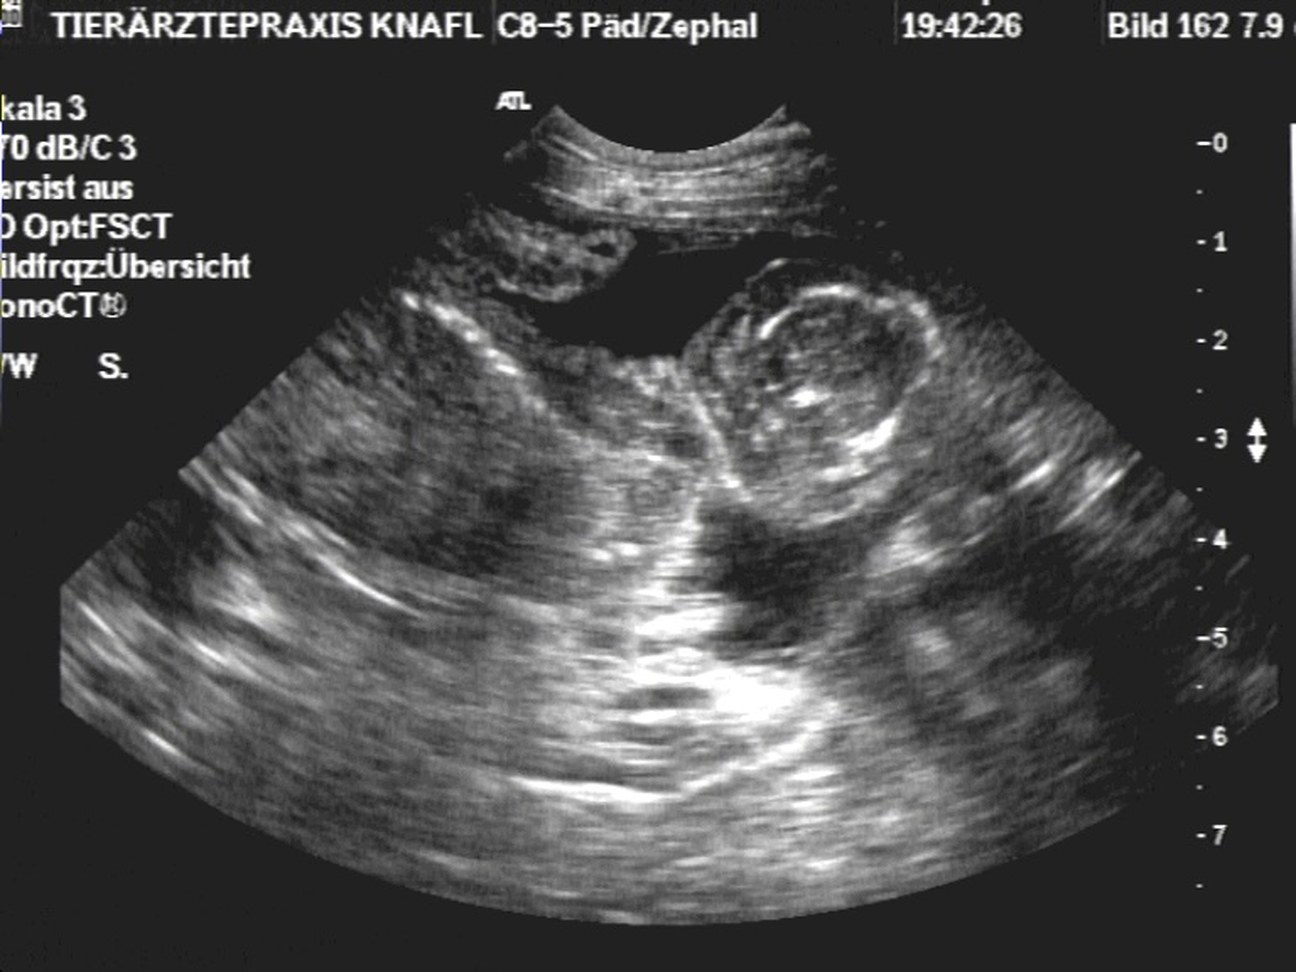

• Ultraschall